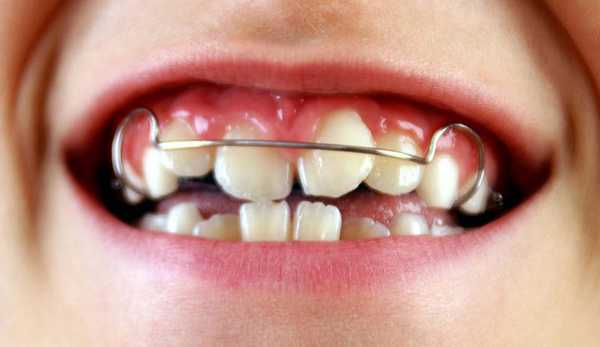

Съемные пластинки устанавливают детям младше 14 лет. Это специальные ортодонтические приспособления из полимерных материалов, которые крепятся к зубам с помощью крючков. Назначение пластинки — формирование челюсти. Если у ребенка от природы челюсть узкая, пластинка стимулирует ее рост. Если челюсть широкая, пластинка не дает ей расширяться еще больше.